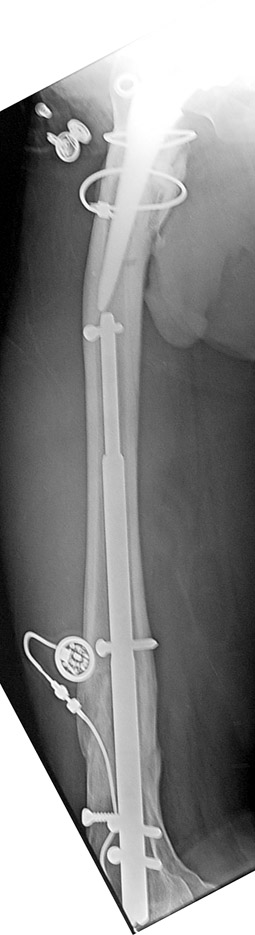

Vaka 2